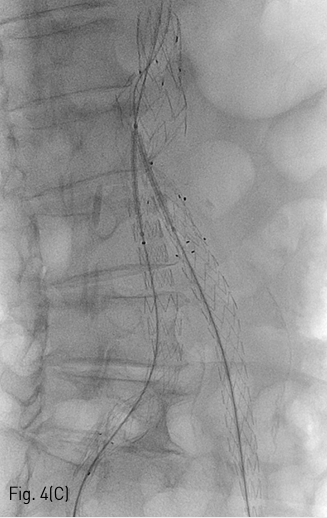

Fig 4C

(C,D) Spot radiography shows introducing stent by kissing method.